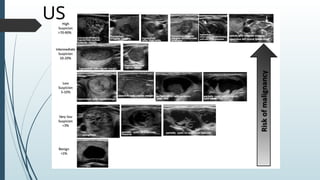

US

BETHESDA SYSTEM